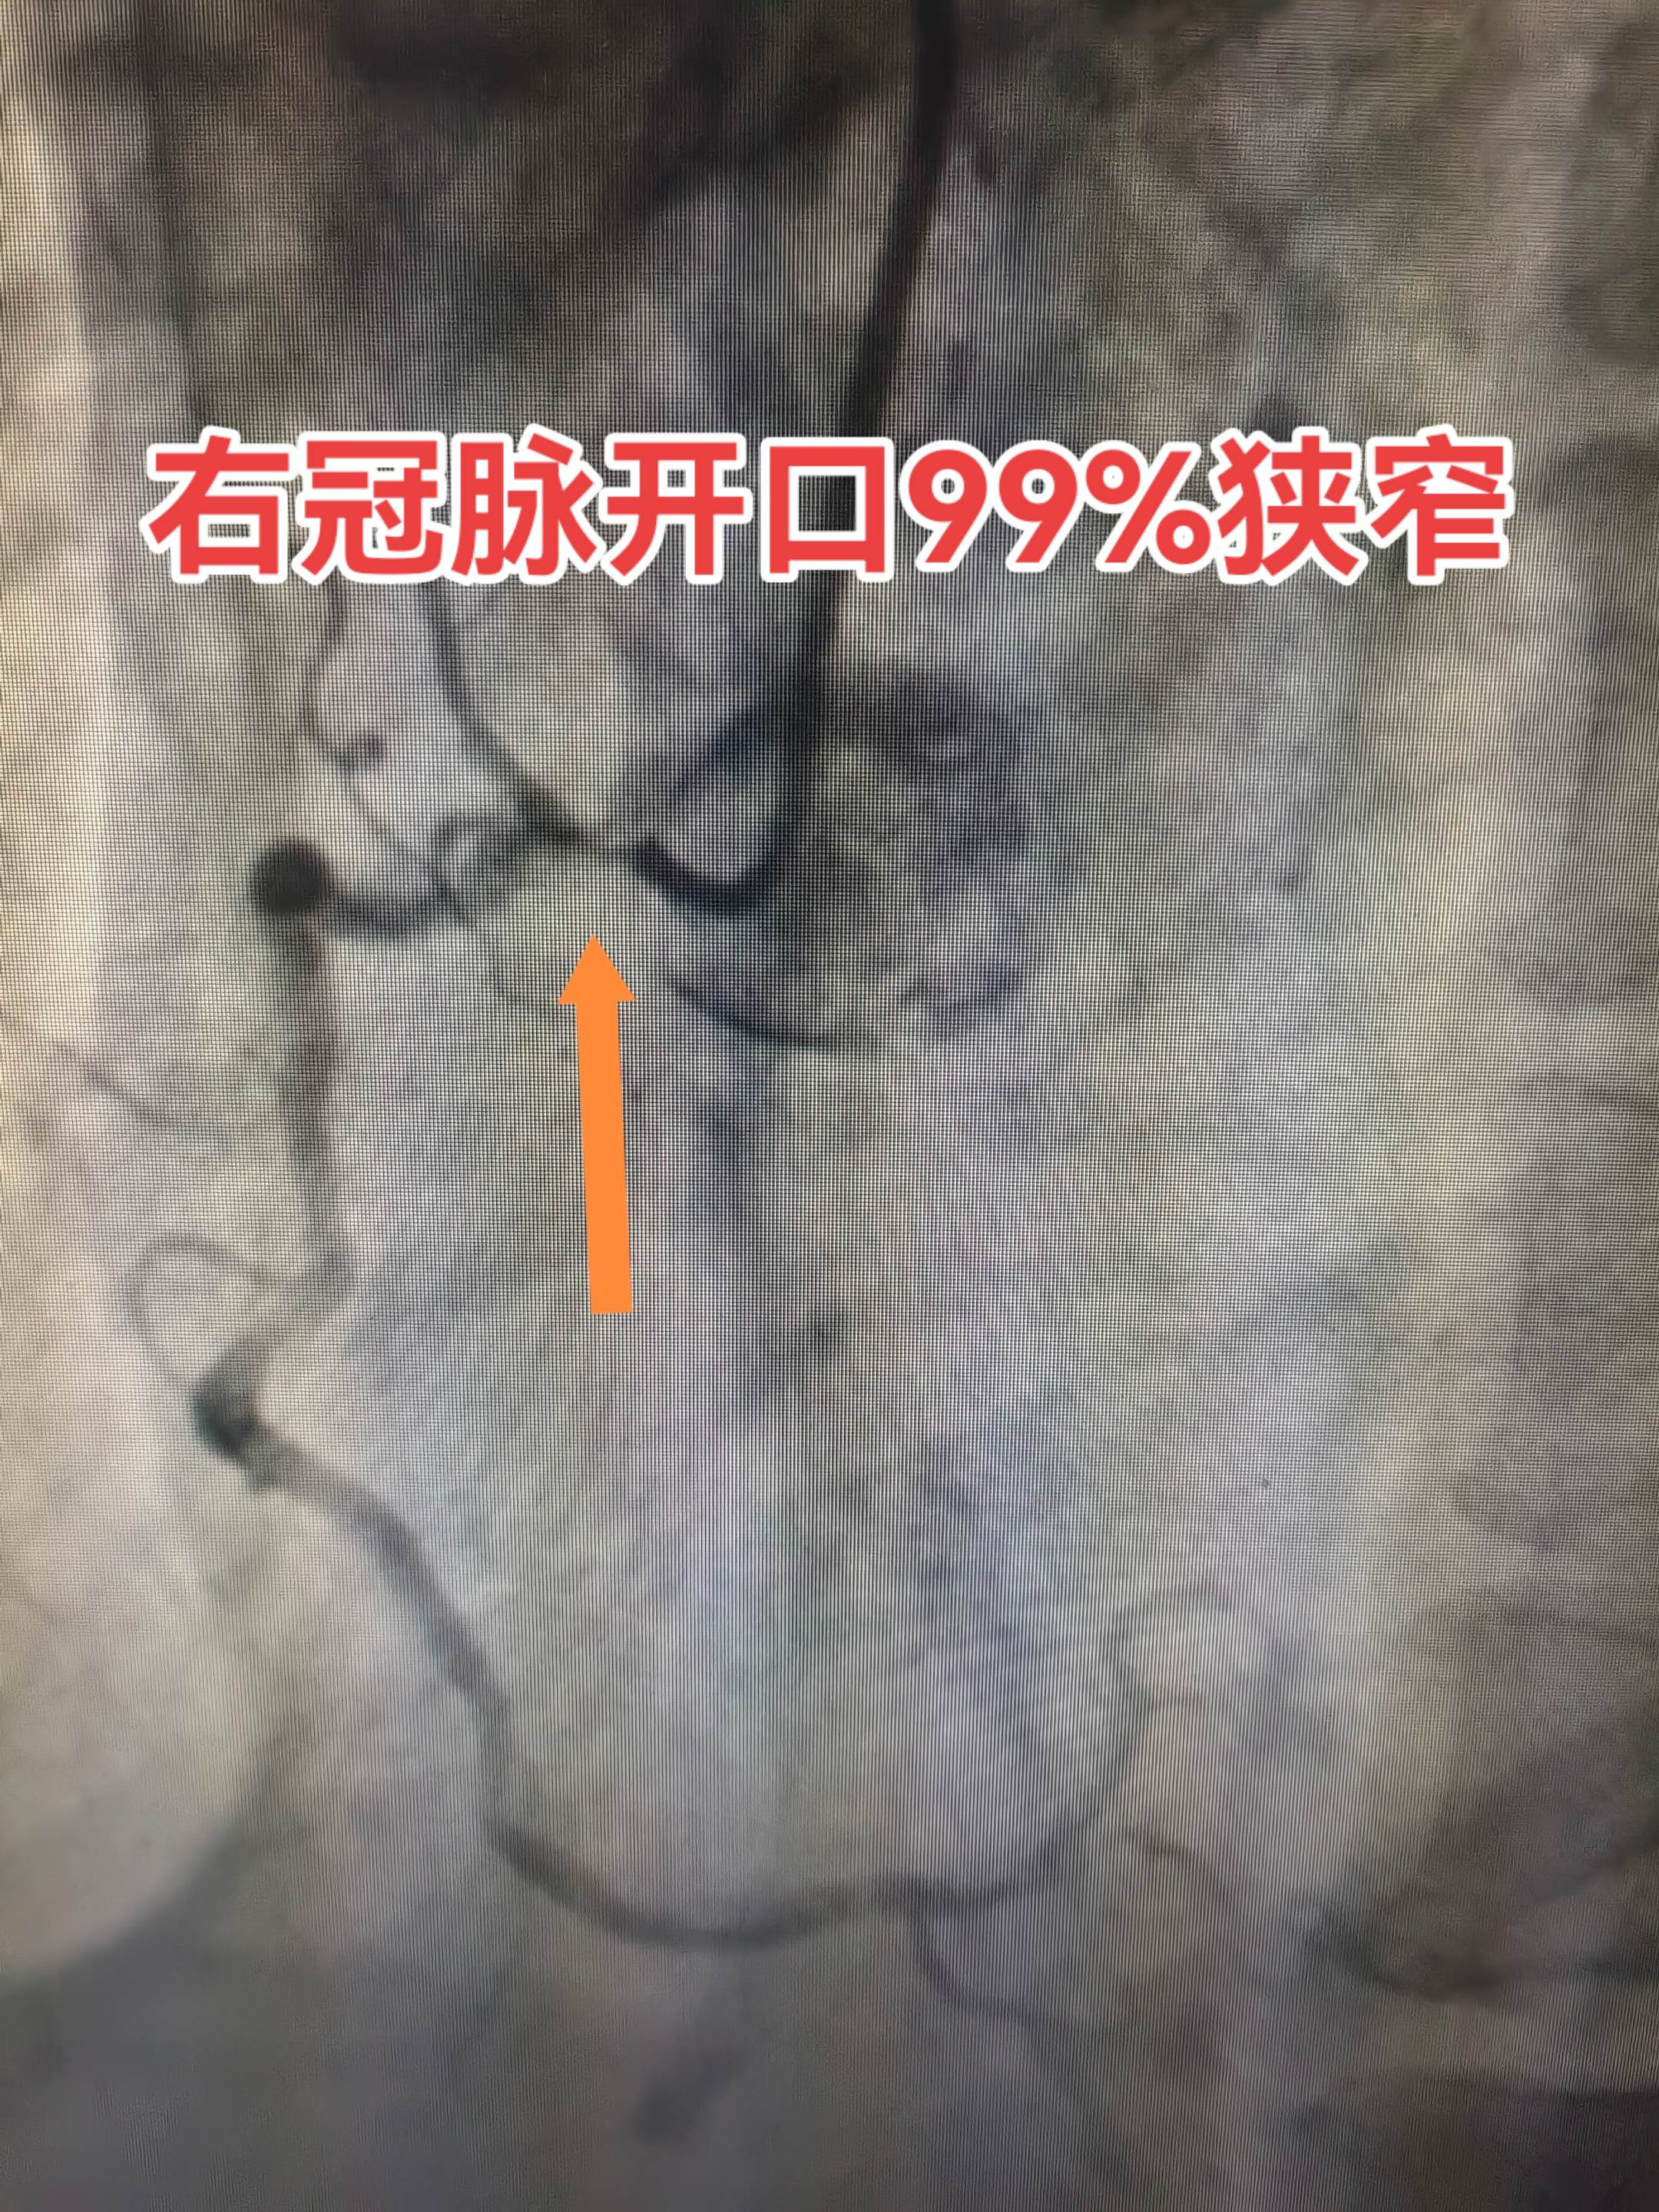

冠脉造影。左右冠脉开口均严重狭窄,诊断为“急性心梗”,太危险了,选择冠脉搭桥治疗。